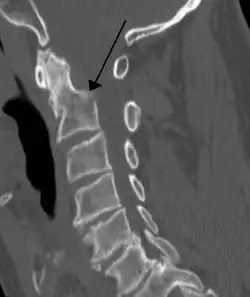

Bei einem Genickbruch – einem Bruch des Zahns des zweiten Halswirbels (Dens axis) – oder einem Riss der Bänder des Dens axis können das verlängerte Mark (Medulla oblongata) und das Rückenmark durchtrennt oder abgequetscht werden. Kommt es dabei zu einer Zerstörung des Atem- und des Kreislaufzentrums, so hat dies den sofortigen Tod zur Folge, vergleichbar einer Enthauptung. Besteht bei Verletzten ohne Spontanatmung der Verdacht auf eine Fraktur des Dens axis, so muss eine notwendige Intubation mit Vorsicht in Neutralstellung der Halswirbelsäule vorgenommen werden, um mögliche oder weitere Schädigungen von verlängertem Mark bzw. Rückenmark zu vermeiden.[2] Rund 70 Prozent der Genickbrüche gehen mit einer Schädigung des Rückenmarks (im Halsbereich) einher, was bei Überlebenden zu dauerhaften Lähmungen führen kann (wie z. B. einer Tetraplegie). Dagegen gibt es auch heilbare Genickbrüche, die – bei korrekter Behandlung – keine dauerhaften Folgeschäden nach sich ziehen.[3]

CT einer Fraktur des 2. Halswirbels